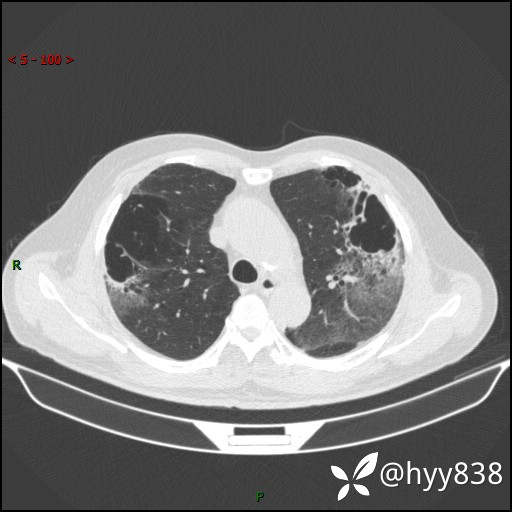

一周后胸部CT